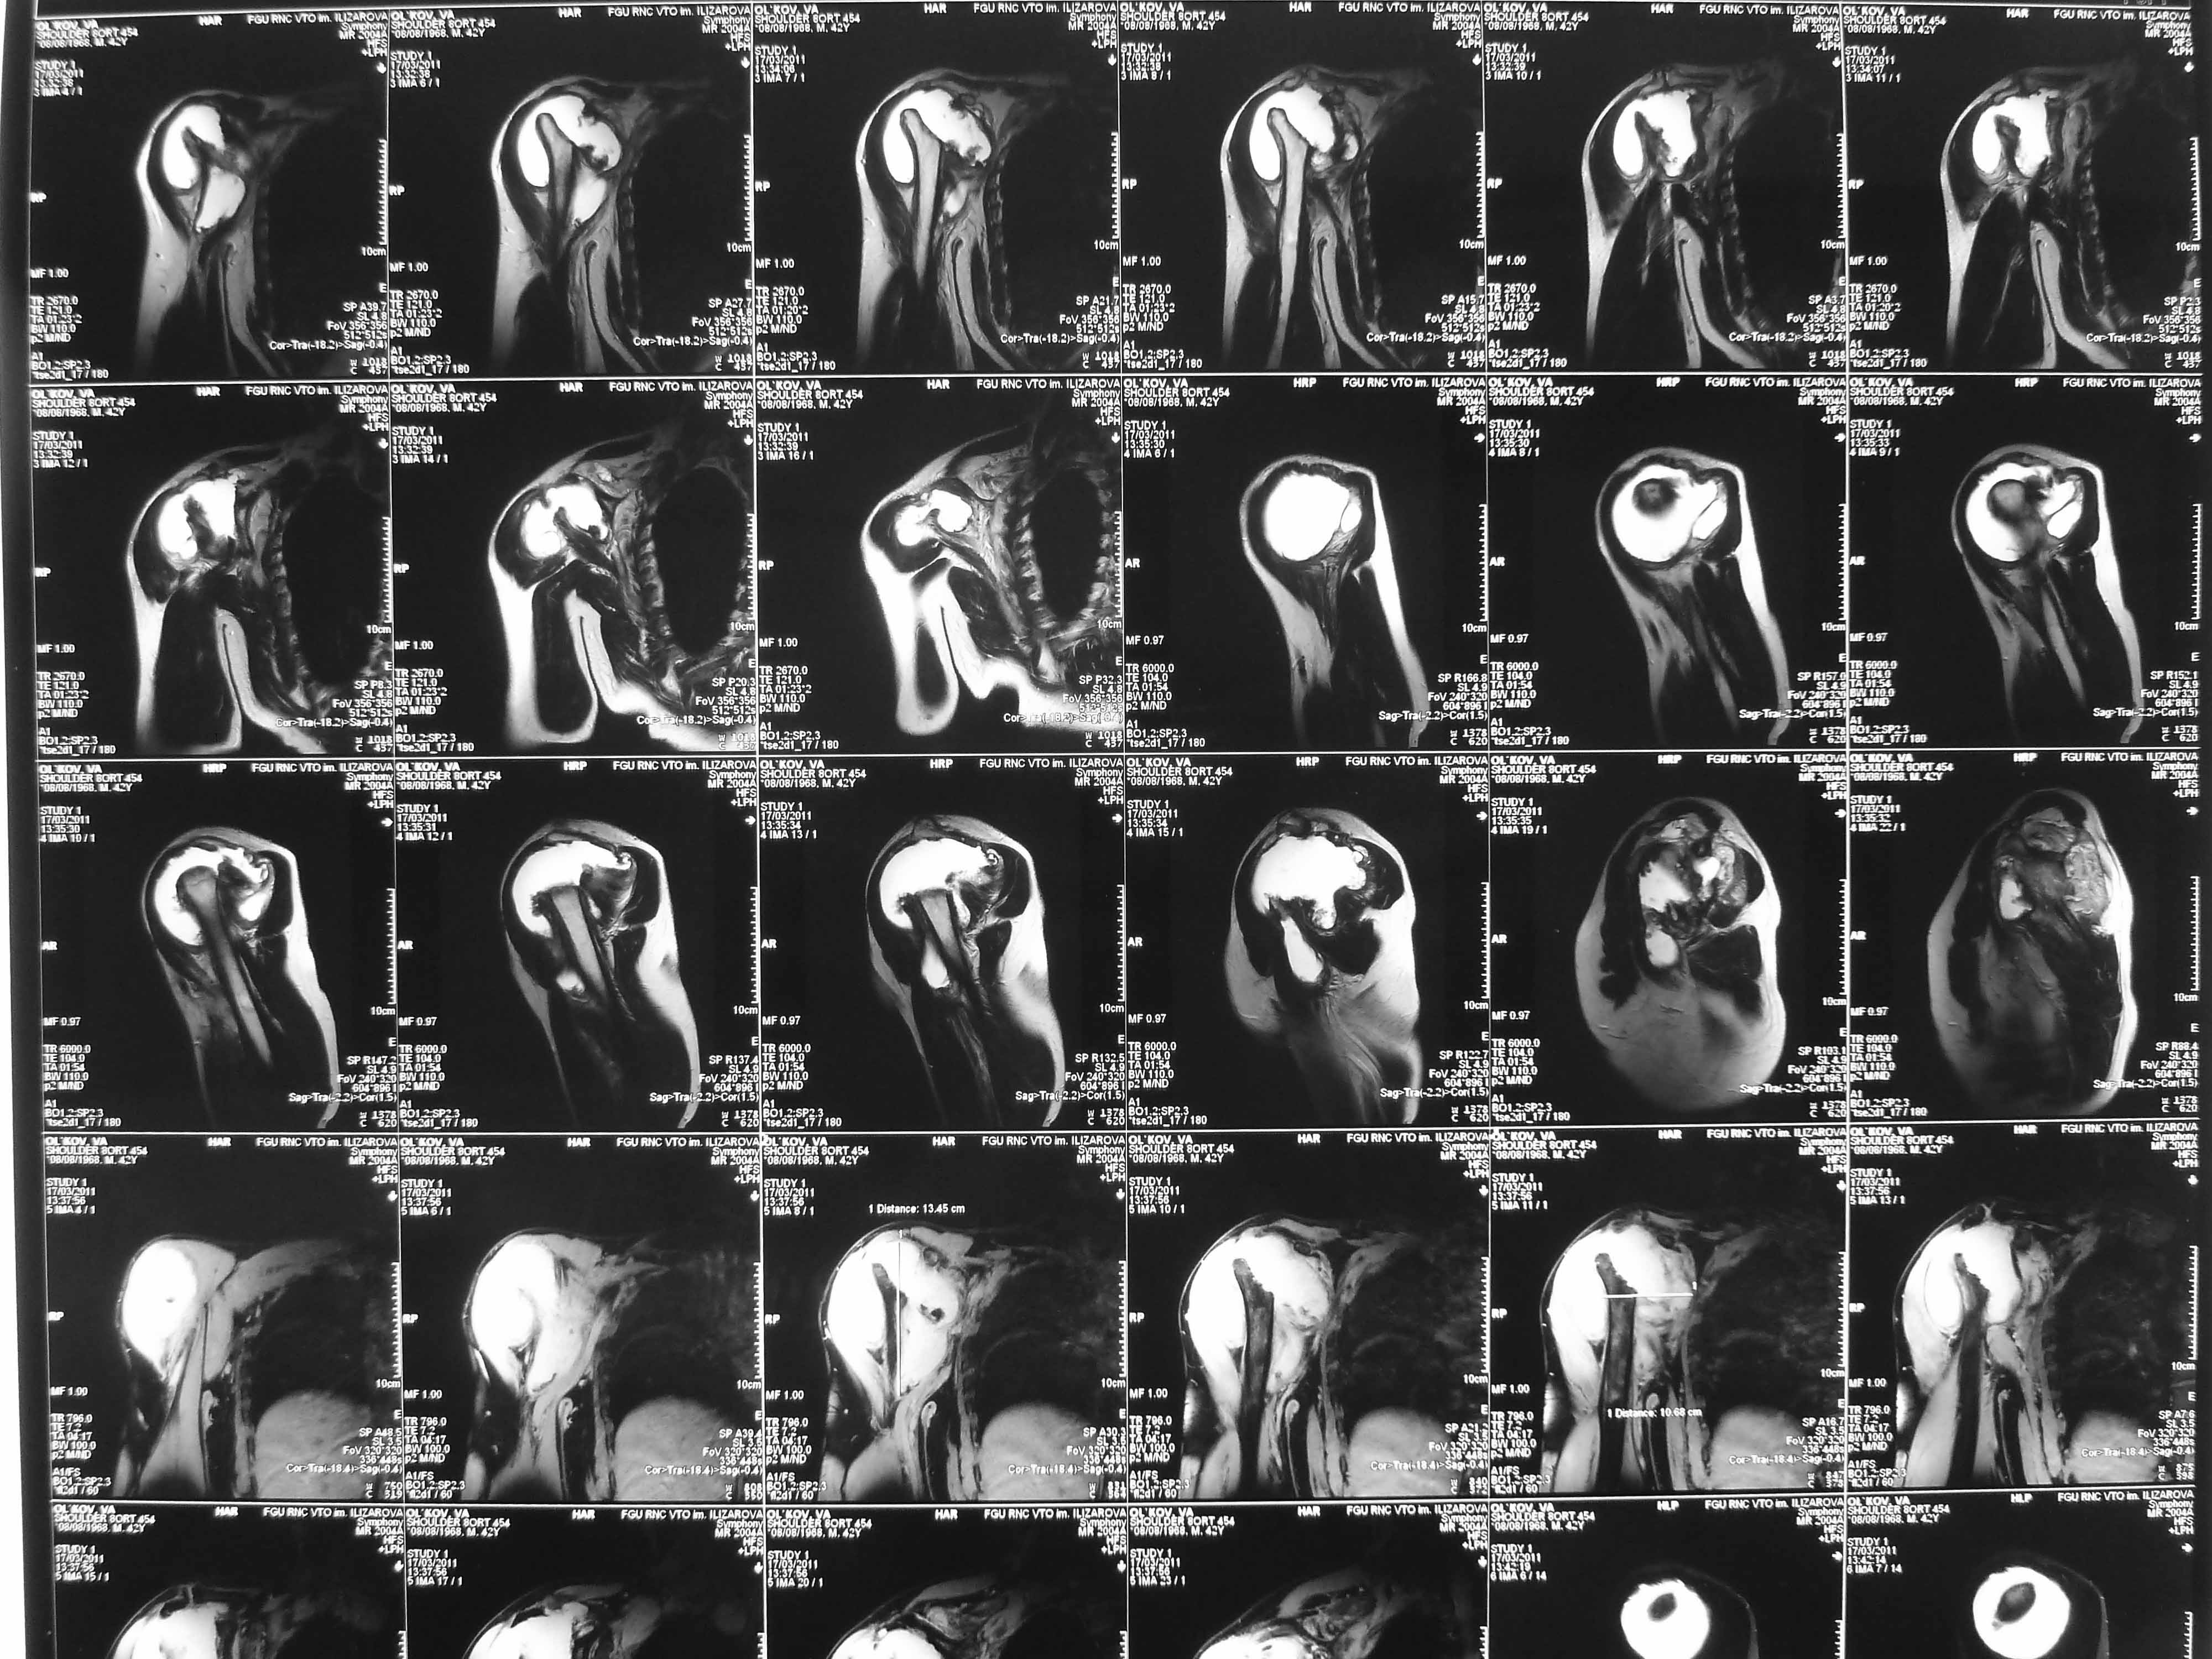

Re: Лизис костей плечевого сустава

Извиняюсь, что-то фотографии сразу не прошли. сейчас исправимся.